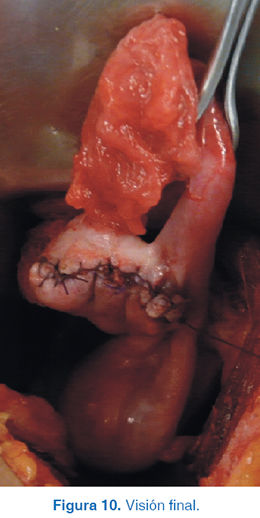

Se realizó laparotomía exploradora con abordaje a través de incisión en la línea media, se encontró tumoración en ovario izquierdo (Figura 7) y se hizo una incisión en la tumoración (Figura 8) hasta realizar salvamento de tejido ovárico (Figura 9) y visión final (Figura 10). El reporte histopatológico fue de teratoma maduro de ovario, con bordes libres de neoplasia. La evolución postoperatoria fue satisfactoria.